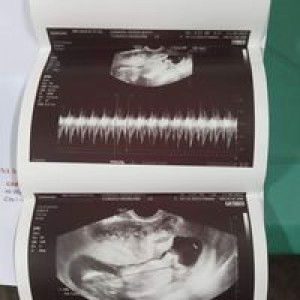

Hi po. Tatanong ko lang po sana kung anu po ang pampababa ng bp kabuwanan ko po ngaun lagi pong napatak ng 140/100 bp ko. Wala naman po kong nararamdaman na masama nagpa urinalysis na din po ko normal naman po. Anu po kayang pwede para mapababa bp ko. TIA